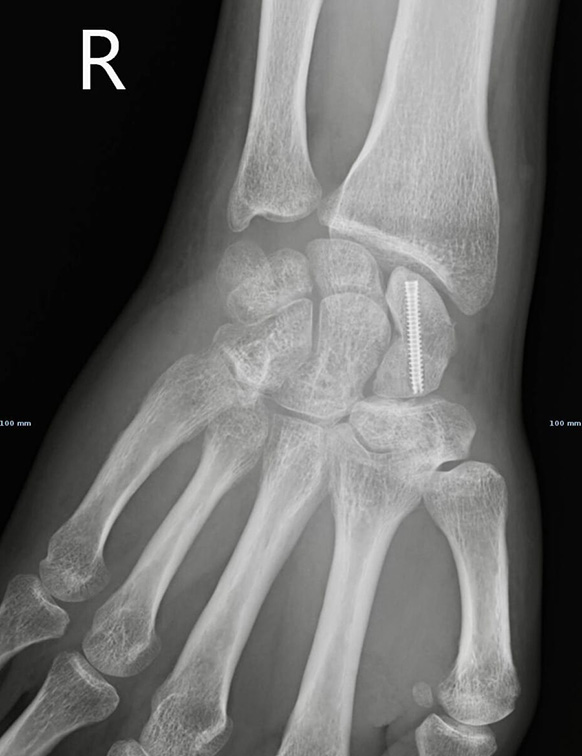

Na maior parte das vezes, é feita uma cirurgia minimamente invasiva (fixação percutânea), com uma cicatriz de 3 ou 4mm, para aplicar um parafuso dentro do osso. Esta técnica está associada a menor dor, menor perturbação da vascularização do escafóide e maior rapidez da cirurgia.

Raio-X após fixação percutânea com parafuso de fractura do escafóide